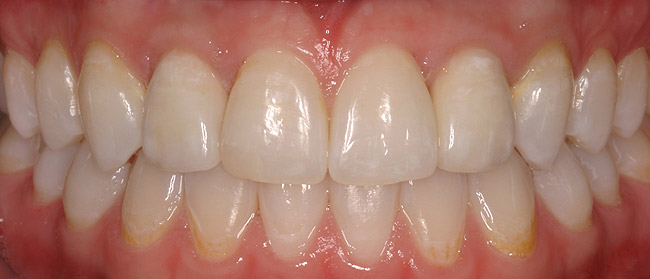

Figure 6a  Upper right central incisor, history of trauma, existing RCT and restoration unsatisfactory.

Figure 6a

Figure 6b  Upper right central incisor, history of trauma, existing RCT and restoration unsatisfactory.

Figure 6b

Figure 6c  Upper right central incisor, history of trauma, existing RCT and restoration unsatisfactory.

Figure 6c

Figure 6d Completed treatment: revised RCT, zirconium post/pressed ceramic core cemented with Panavia 21¬Æ Resin Cement (Kuraray Dental). All-ceramic full-coverage crown cemented with Kerr NX3 Nexus¬Æ Third Generation Dual Cure Resin cement. Implant therapy not indicated.

Figure 6d

Figure 6e  Completed treatment: revised RCT, zirconium post/pressed ceramic core cemented with Panavia 21¬Æ Resin Cement (Kuraray Dental). All-ceramic full-coverage crown cemented with Kerr NX3 Nexus¬Æ Third Generation Dual Cure Resin cement. Implant therapy not indicated.

Figure 6e

Figure 6f  Completed treatment: revised RCT, zirconium post/pressed ceramic core cemented with Panavia 21¬Æ Resin Cement (Kuraray Dental). All-ceramic full-coverage crown cemented with Kerr NX3 Nexus¬Æ Third Generation Dual Cure Resin cement. Implant therapy not indicated.

Figure 6f